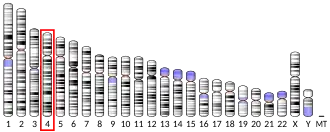

- Huppi K, Siwarski D, Pisegna JR, Wank S (Feb 1995). "Chromosomal localization of the gastric and brain receptors for cholecystokinin (CCKAR and CCKBR) in human and mouse". Genomics. 25 (3): 727–9. doi:10.1016/0888-7543(95)80018-H. PMC 6736545. PMID 7759110.

- de Weerth A, Pisegna JR, Huppi K, Wank SA (Jul 1993). "Molecular cloning, functional expression and chromosomal localization of the human cholecystokinin type A receptor". Biochemical and Biophysical Research Communications. 194 (2): 811–8. doi:10.1006/bbrc.1993.1894. PMID 8343165.

- Inoue H, Iannotti CA, Welling CM, Veile R, Donis-Keller H, Permutt MA (Jun 1997). "Human cholecystokinin type A receptor gene: cytogenetic localization, physical mapping, and identification of two missense variants in patients with obesity and non-insulin-dependent diabetes mellitus (NIDDM)". Genomics. 42 (2): 331–5. doi:10.1006/geno.1997.4749. PMID 9192855.